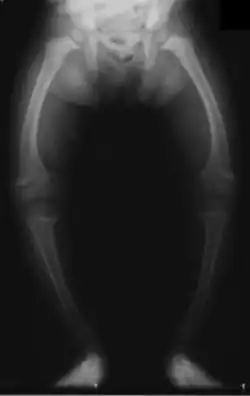

X-ray of the legs in a two year old child with rickets showing bowing of the femur and low bone density.

Rickets, a childhood disease, is characterized by impeded growth and soft, weak, deformed long bones that bend and bow under their weight as children start to walk. Maternal vitamin D deficiency can cause fetal bone defects from before birth and impairment of bone quality after birth.[81][82] Rickets typically appear between 3 and 18 months of age.[83] This condition can be caused by vitamin D, calcium or phosphorus deficiency.[84] Vitamin D deficiency remains the main cause of rickets among young infants in most countries because breast milk is low in vitamin D, and darker skin, social customs, and climatic conditions can contribute to inadequate sun exposure. A post-weaning Western omnivore diet characterized by high intakes of meat, fish, eggs and vitamin D fortified milk is protective, whereas low intakes of those foods and high cereal/grain intake contribute to risk.[85][86][87] For young children with rickets, supplementation with vitamin D plus calcium was superior to the vitamin alone for bone healing.[88][89]